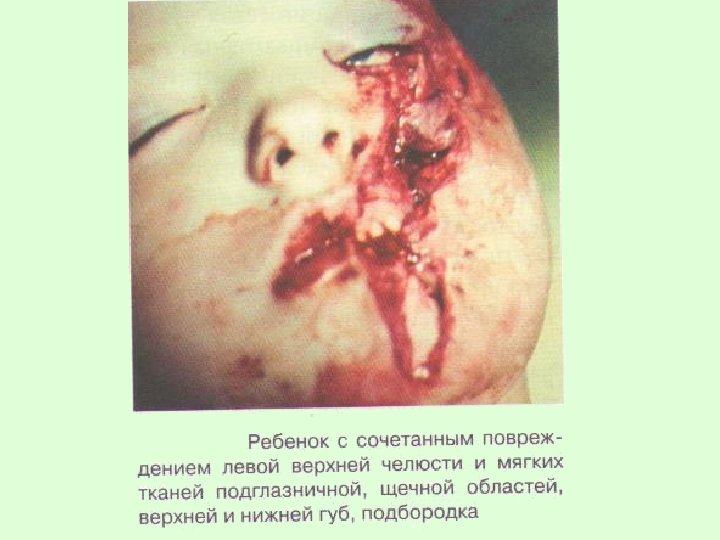

Сочетанная травма характеризуется повреждением твердых и мягких тканей разных анатомо-топографических участков челюстно-лицевой области. Такая травма в 82 % случаев возникает у детей после 8 лет. Среди них мальчики составляют две трети.

У детей сочетанные повреждения чаще всего возникают в результате автокатастроф, падения с высоты, во время спортивных занятий и характеризуются переломами челюстей, травмами зубов, гематомами мягких тканей.

Каждая из составляющих сочетанной травмы отягощает течение процесса выздоровления. Кроме того, при сочетании травмы челюстей с ранами, сопровождающимися дефектами тканей, или лоскутными ранами возникает угроза развитияразличных видов асфиксий.